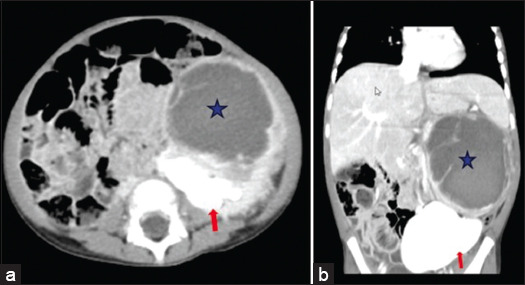

Case description: We are reporting a case report of Wilms tumor in a 3-year-old girl who presented with a huge left flank mass with cross-fused renal ectopia. After the initial workup and triphasic computed tomography scan of the chest, abdomen, and pelvis for confirmation of diagnosis and metastasis, the patient underwent image-guided tissue biopsy, followed by neoadjuvant chemotherapy, left radical nephrectomy with separation of fused right ectopic renal moiety, and adjuvant chemoradiation.